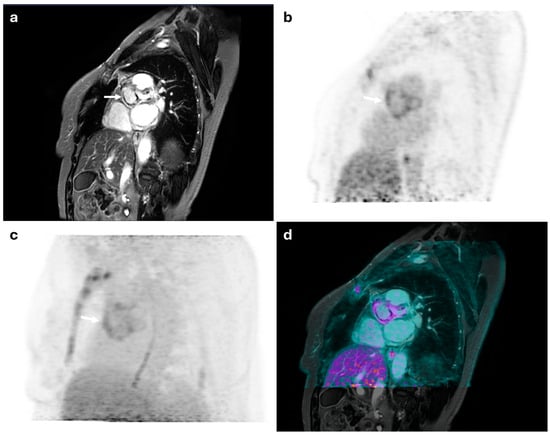

Figure 1.

45-year-old female with suspected mitral valve endocarditis. (a) shows a cardiac MRI image revealing a mobile pseudonodular lesion on the posterolateral leaflet of the mitral valve, exhibiting late gadolinium enhancement (white arrow), which was inconclusive for the presence of inflammatory vegetation. (b) displays an FDG-PET image with pathological radiotracer uptake (SUVmax: 6.5). The integrated PET/MRI findings were diagnostic of mitral valve endocarditis (c,d).